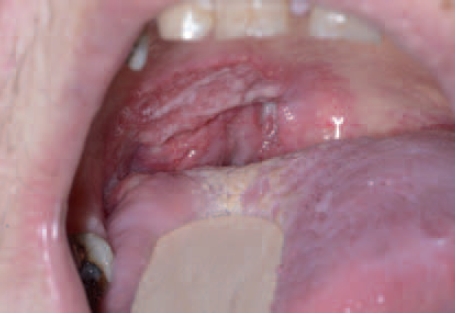

Een eenzijdig vergrote tonsil [

figuur 2] komt weinig voor in de Nederlandse huisartsenpraktijk. In een onderzoek heeft men 267 tonsillectomieën geanalyseerd, waarvan er bij 30 sprake was van asymmetrie.

3 De patiënten varieerden in leeftijd van 7 tot 84 jaar. Bij 80% van de 30 patiënten met een eenzijdig vergrote tonsil was de aandoening benigne en bij 20% was deze maligne.

Eenzijdige vergroting van de tonsil kan het gevolg zijn van een infectie, een chronische ontsteking en nieuwvormingen. Veruit de meest voorkomende infectieuze oorzaak van een eenzijdig vergrote tonsil is het dreigend peritonsillair abces. Wat betreft nieuwvormingen gaat het in de meerderheid van de gevallen om lymfomen of plaveiselcelcarcinomen [

figuur 1]. Zeldzamer zijn de plasmocytomen, leukemie en metastasen. Verschillende bevindingen zijn gerelateerd aan een vergrote kans op een maligniteit: cervicale lymfadenopathie, een klinisch verdachte tonsil (ulceratie, irregulariteit, abnormale pigmentatie) en de aanwezigheid van begeleidende systemische symptomen, zoals koorts, nachtzweten, dysfagie en gewichtsverlies.